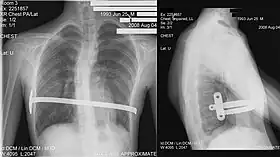

Bar removal

After a period of two to four years,[3]: 343 the surgical stainless steel bar is removed from the patient's chest. This procedure lasts approximately ninety minutes. The length of time that the patient stays at the hospital following the bar removal procedure varies, depending on the amount of new bone growth surrounding the bar. Accordingly, the length of time may range from a few hours to several days, or up to one week.